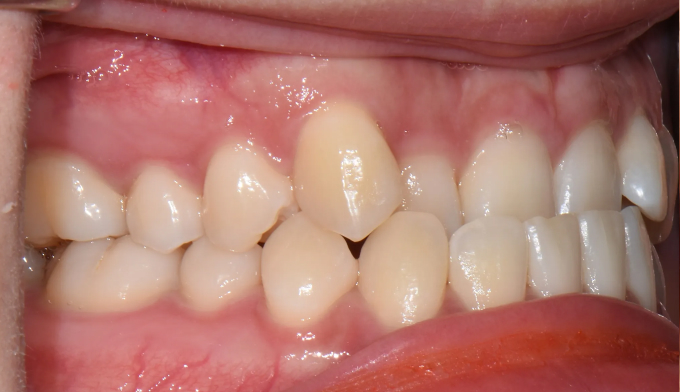

성인에서의 주걱턱은 흔히들 교정치료로 개선 불가능하다고 알고 있습니다. 주걱턱을 해소하기 위해서는 양악수술만이 답이라고 생각합니다.

턱의 성장이 과도하여 안모의 개선이 필요한 경우, 또는 치아가 이동해야할 양이 교정치료로 가능한 양보다 너무 큰 경우를 제외하고 대부분의 주걱턱 또는 반대교합은 교정치료로 해결이 가능합니다.

주걱턱이라고 하여 내원하신분들 대부분 위턱과 아래턱의 비율은 정상이지만 앞니만 반대로 물리는 반대교합의 경우가 많습니다. 어렵지않게 앞니를 배열하여 보다 더 매력적인 미소를 갖는 얼굴을 만들어줄 수 있습니다,

총 치료기간은 15개월 소요되었습니다.

거꾸로 물려있던 앞니를 앞으로 보내면서, 아래치열은 사랑니발치 후 미니스크류를 이용하여 후방이동시켰습니다.